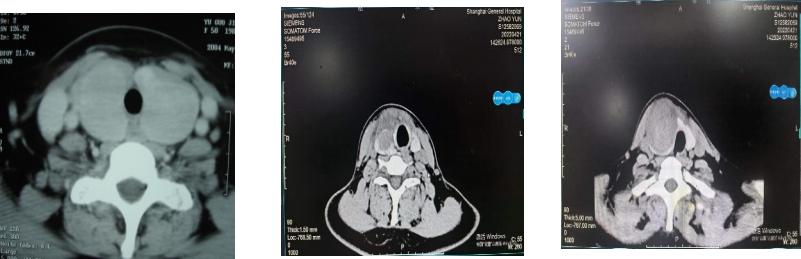

(3)甲状腺CT和磁共振(MRI):不作为甲状腺结节常规检查手段,但大的或者恶性结节,手术前检查,可以帮助医生判断结节与周围组织的关系,如结节周围淋巴结情况,以及是否压迫周围组织(图6),为后期治疗提供依据。而价格更昂贵的PET-CT,通常用于甲状腺癌患者,帮助寻找甲状腺以外器官是否有转移,尤其是肺和骨质的转移。

图6. 甲状腺肿大和甲状腺结节的CT表现